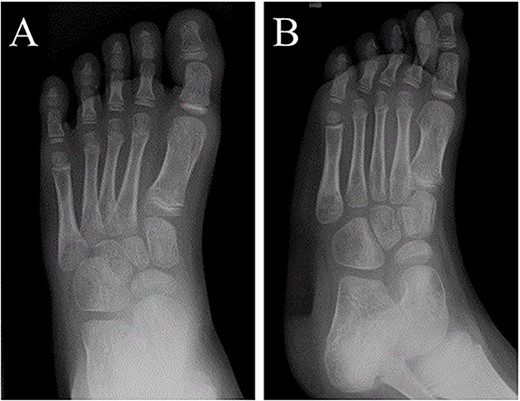

A 21-month-old Japanese female infant presented with a swollen mass on the dorsolateral aspect of the left foot. Her parents noticed the mass and brought the patient to our hospital. The patient had no past medical histories or complications prior to the occurrence. In addition, she received the BCG vaccine at the age of 4 months in Japan. At first visit to our hospital, physical examination revealed the ~3 × 3 cm mass was located on the dorsolateral aspect of the left foot and was hard accompanied by local heat (Fig. 1). Plain radiographs of the left foot showed a lytic lesion without periosteal reaction in the fifth metatarsal bone (Fig. 2). Magnetic resonance imaging (MRI) showed an isointense lesion on T1-weighted images and a hyperintense lesion on T2-weighted images around and within fifth metatarsal (Fig. 3). Gallium scintigraphy revealed intense uptake in the patient’s left foot (Fig. 4). In addition, laboratory examination was within normal. Based on medical history, clinical and imaging findings, we considered the possibility of neoplasia or osteomyelitis and performed an open debridement and biopsy of the lesion to make a diagnosis. The lesion was yellow and consisted of weak, adipose-like tissue that surrounded and continued into the inferior of the fifth metatarsal bone (Fig. 5). The lesion inside and outside the bone was resected as much as possible. Histopathologic examination of the lesion showed granulomatous inflammation including anaplastic giant cells, Langerhans-type giant cells and caseous necrosis (Fig. 6). Based on these results, TB or BCG osteomyelitis was considered as a diagnosis. The tuberculin test was positive, but the QuantiFERON TB test was negative. In addition, samples analyzed using polymerase chain reaction did not identify M. tuberculosis, but did identify the BCG Tokyo-172 strain. Per these findings, the patient was diagnosed with BCG osteomyelitis of the fifth metatarsal and oral treatment with anti-TB medicine including isoniazid (100 mg/day) and rifampicin (150 mg/day) was started. Clinical findings included reduction in swelling of the mass and gradual remodeling of the lytic lesion of the fifth metatarsal on plain radiographs (Fig. 7). However, 10 months after starting the anti-TB treatment, the mass recurred, and MRI revealed a residual high-intensity lesion around and inside the fifth metatarsal on T2-weighted fat-suppressed images (Fig. 8). It was determined that the lesion was difficult to control with anti-TB treatment alone, so an open debridement for the lesion was performed again. Histopathologic examination of the lesion revealed an epithelioid granuloma with necrosis. Therefore, the anti-TB treatment was continued. Six months after the second surgery, clinical and radiographic image findings showed complete improvement (Fig. 9). As a result, anti-TB treatment was ended. At the time of writing this report, 8 years after starting anti-TB treatment, there has been no recurrence.

At 6 months after the second surgery, image findings on plain radiographs completely improved on (A) anteroposterior and (B) oblique views.